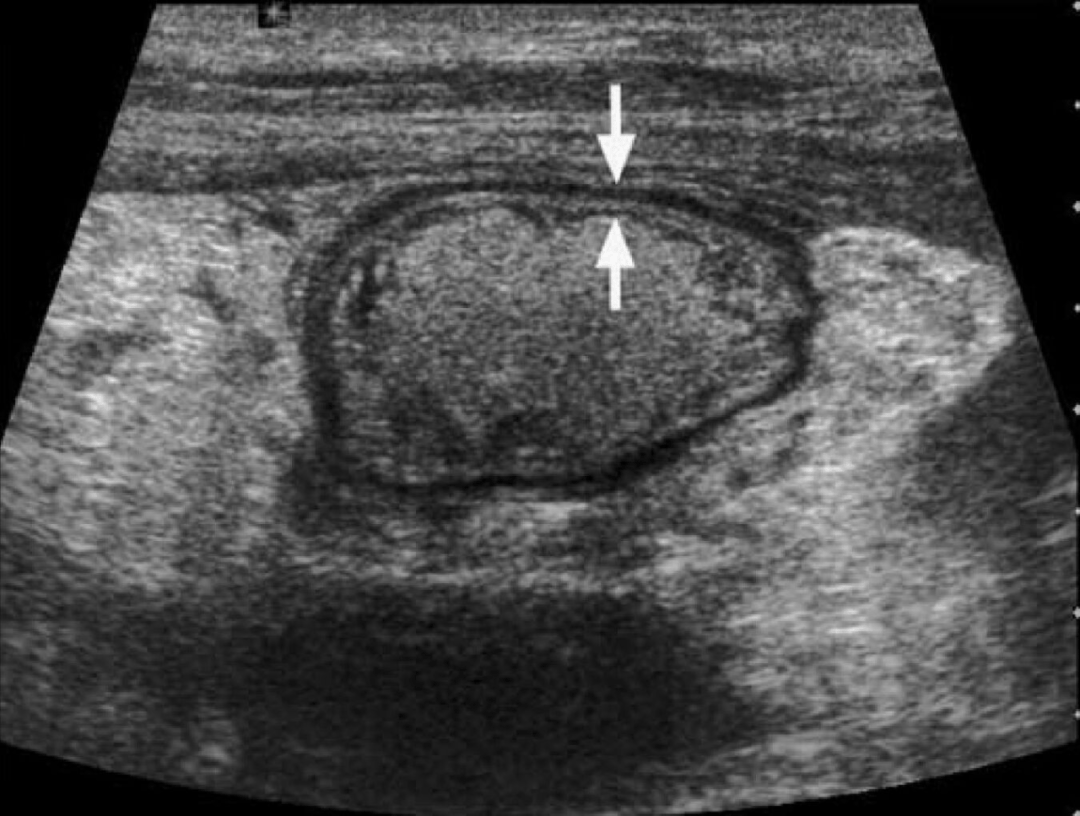

图3:扩张淋巴管。同病例1,超声显示在“白肠”(箭头所示)内可见多处细线状无回声区(测量标记处),为扩张的淋巴管。Hint:淋巴管扩张的形成机制与分枝杆菌阻塞淋巴回流、肠壁内乳糜微粒淤积有关。